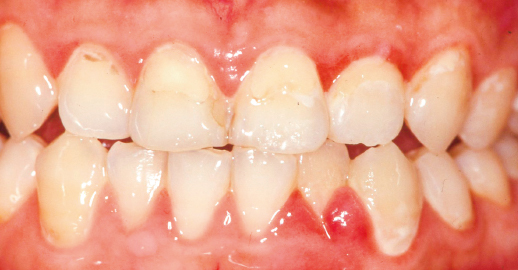

2,歯周病、歯肉炎;歯肉炎は、歯垢(プラーク)や歯石の細菌が原因で起こります。ブラッシング不足などでプラークが蓄積すると歯肉の炎症が生じます。炎症が生じると歯肉の腫れや易出血が起ります。この段階の腫れはしっかりブラッシングを行う事で消失していきます。しかし、この状態を放置すると歯周炎に移行していきます。歯周炎に移行してしまうと歯茎からの排膿や出血が生じます。この状態ではブラッシングを行ってもあまり改善しません。専門的なクリーニングや抗生物質の服用が必要となって来ます。